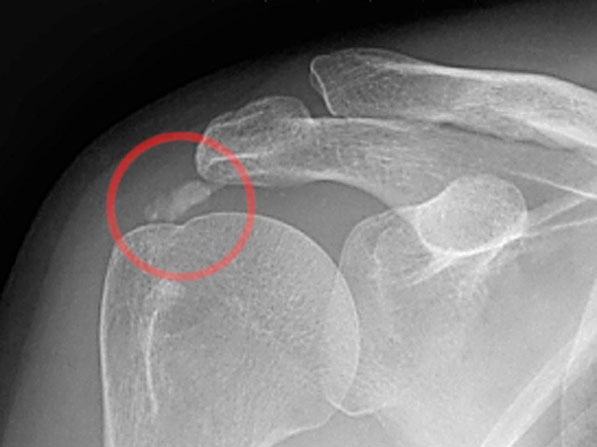

A váll meszes íngyulladásának (calcificáló tendinitis) létezik műtéti megoldása, amennyiben a konzervatív kezelés nem hoz tartós eredményt. A műtét lényege, hogy rotátorköpeny ínainak állományában felrakódott mész csomót sebészi úton kiürítjük. Az artroszkópos technikával végzett beavatkozás során rotátorköpeny külső rétegét szétválasztjuk és az alatta levő meszes ’fészeket’ alaposan kiürítjük. Előfordul, hogy az alapos mész eltávolítás érdekében az ínon nagyobb nyitást kell végezni. Ilyenkor az íngyógyulás érdekében a köpeny folytonosságát helyre kell állítani, ami a teljes felépülési időt megnyújthatja. Ezt a beavatkozást általában kiegészítjük fentiekben részletezett subacromiális decompresszióval. Rehabilitáció hozzávetőlegesen 3 hónapot is igénybe vehet.

Artroszkópos kalcium depozit kiürítés